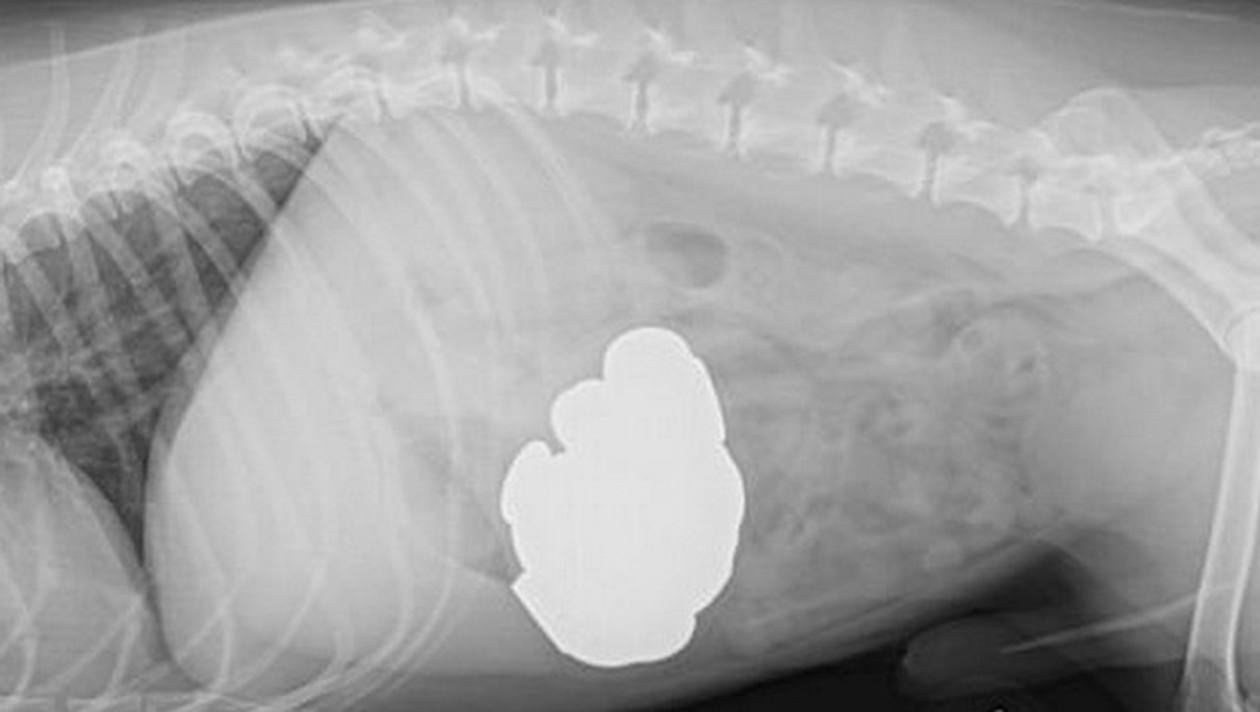

Nu mai putin de 111 au gasit medicii veterinari in stomacul cainelui, care a fost operat de urgenta.

Tim Kelleher, stapanaul nastrusnicului animalut, a petrecut doua ore de groaza pana cand medicii au reusit sa-i scoata cele 111 modene din stomac, cate cinci deodata.